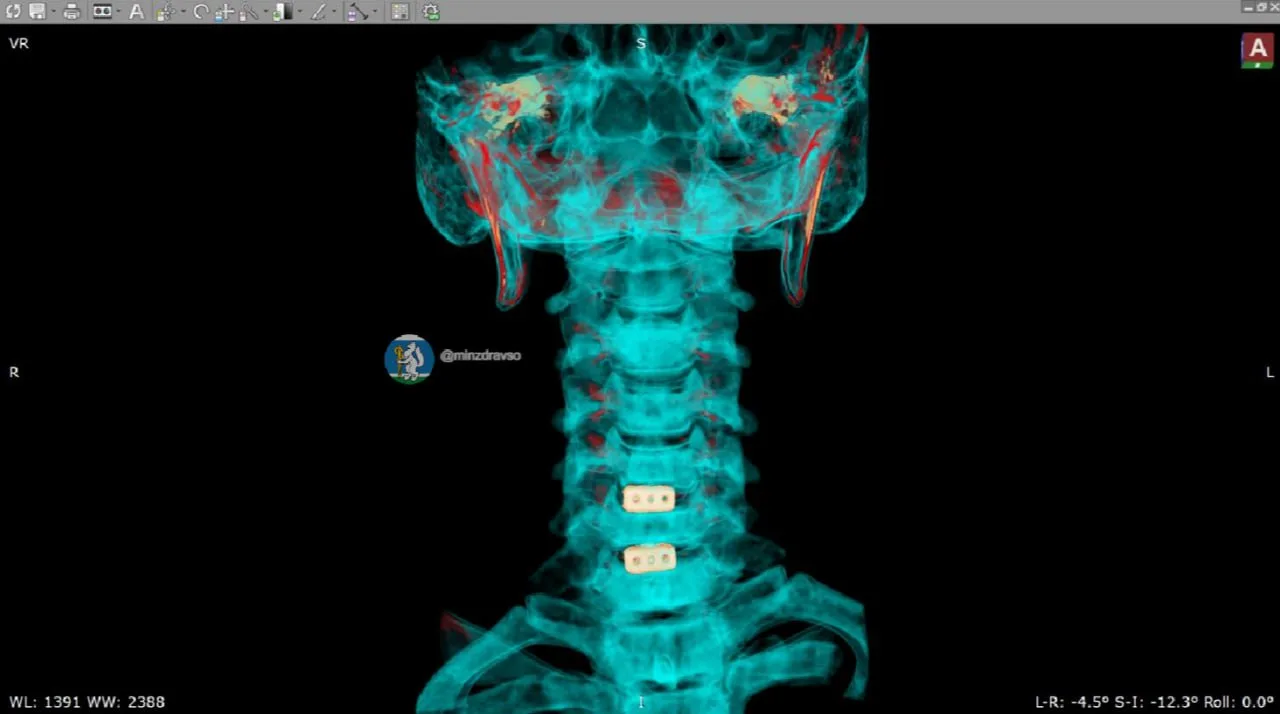

🏍 Свобода, скорость, риск: как одно путешествие могло закончиться трагедией — и почему экипировка важнее адреналина

Он мечтал о дороге. О ветре в лицо, о рёве мотора, о километрах, которые летят как один миг. Молодой житель Рефтинского сел на мотоцикл, чтобы почувствовать свободу. Но иногда одно неверное движение, один скользкий поворот, одна секунда невнимательности — и путешествие превращается в борьбу за жизнь.

🔥 Свердловские врачи трех больниц восстановили здоровье 27-летнего программиста, который мечтал о путешествии по Азии.

Успев посетить 15 стран, он попал в аварию на мотоцикле. У мужчины диагностировали перелом головки плечевой кости в четырёх местах, и долгожданное путешествие пришлось прервать. Через сутки после получения травмы Эдуард в ортезе вернулся в родной регион и обратился за помощью к медикам.

🏥 Чтобы помочь Эдуарду, специалисты Центральной городской клинической больницы №23 Екатеринбурга приняли решение выполнить открытую операцию с применением фиксирующих металлических пластин и спиц. В процессе вмешательства классическую методику модифицировали: в безопасной зоне для увеличения прочности конструкции использовали дополнительную пластину-фиксатор, что позволило пациенту начать движение плечом и рукой уже в первые сутки после операции.

Эдуард находился под наблюдением врачей Городской больницы Асбеста, которые направили молодого человека на реабилитацию в Областную специализированную больницу медицинской реабилитации «Липовка», о которой мы подробно рассказали здесь.